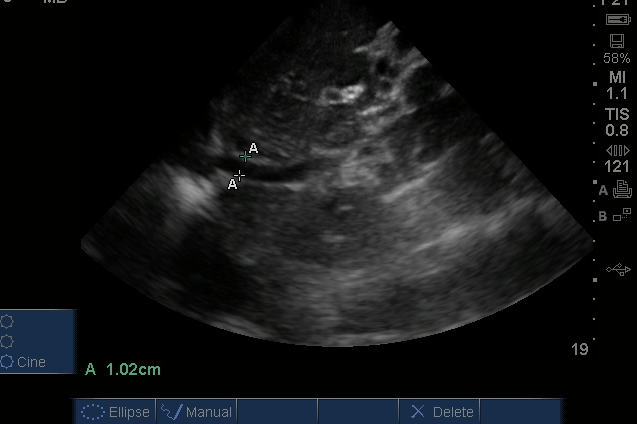

The Pump: a subxiphoid view:

So, we see that there is no pericardial effusion/tamponade or severe RV dilation and strain to suggest pulmonary embolism, and good contractility to rule out significant MI, but there is free intraperitoneal fluid surrounding the liver – could this be due to his cancer, trauma, a ruptured aorta, or third spacing?